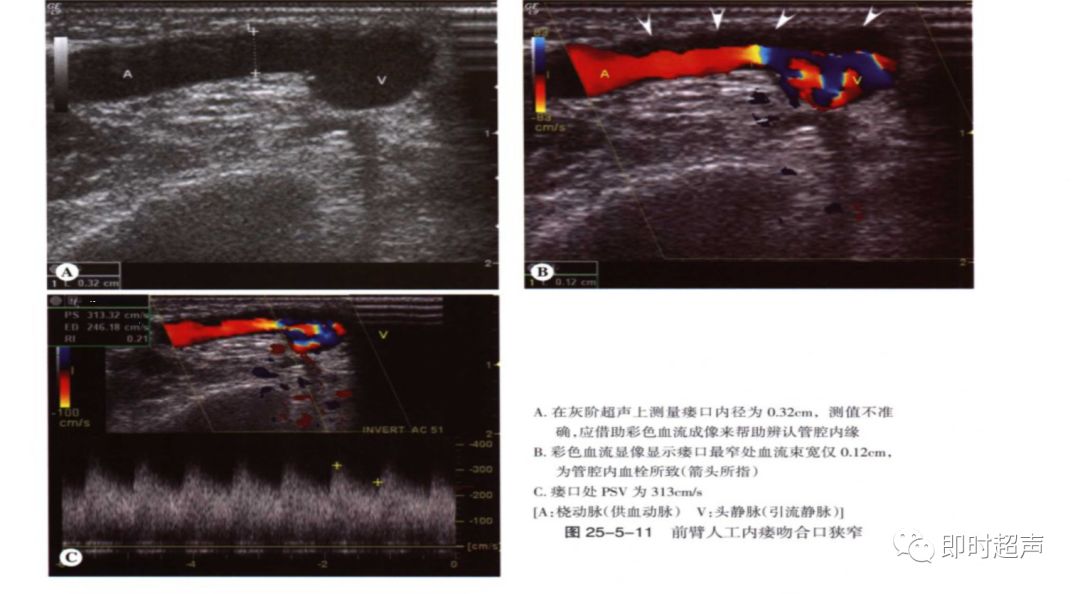

狭窄:狭窄大多发生于吻合口及静脉流出道。

超声表现:多普勒分析:狭窄处直接征象:PSV>4m/s(直径狭窄率50%以上),间接征象:供血动脉或肱动脉呈高阻波形,血流量减少。

(2)吻合口狭窄:分别测量吻合口处PSV及其上游2cm处动脉PSV,计算比值, ≥3.0时考虑吻合口狭窄。

吻合口内径正常约3-5mm,若小于2.5mm,血流异常考虑吻合口狭窄。